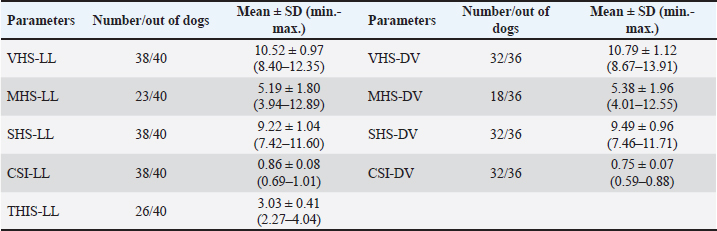

Objective methods for the assessment of cardiac size and shape used in this study were: modified VHS, MHS, SHS, this, and CSI. In each objective methods of cardiac silhouette measurement, the LA and SA were measured in the same way. In LL radiographs, cardiac LA length (mm) was the line extending from the ventral border of the left mainstem bronchus to the most distant ventral contour of the cardiac apex. SA length (mm) was the line drawn perpendicular to the cardiac LA on the widest part of the cardiac silhouette. In DV radiographs, the LA was drawn as the line starting from the dorsal margin of the right atrium projection to the left apex. The SA was drawn perpendicular to the LA at the widest part of the cardiac silhouette (Fig. 1A and B).

Fig. 1. A and B. Measurements of LA and SA in LL (A) and DV (B) views, with marked T4, S4, M, TI length: LA – long axis, SA – short axis, T4 - the length (mm) of the body and caudal disc of the T4vertebra, S4 - the length (mm) of the S4, M – the length (mm) of the M, TI - the length (mm) of a dog’s TI. Modified vertebral heart sizeThe cardiac LA and SA in LL view were measured as previously described, added up, and then transformed from mm into whole and 0.01 of VHS units (v), by dividing the sum of both axes by the length (mm) of the body and caudal disc of the T4 (VHS-LL) (Spasojević Kosić et al., 2007). The same was done to calculate the cardiac VHS in DV radiographs (VHS-DV). Manubrium heart scoreThe sum of the measured cardiac LA and SA (in mm) was normalized by the corresponding M length (mm) according to the method described by Mostafa and Berry (2017). The same was done for both MHS in LL and in DV radiographs (MHS-LL and MHS-DV). Sternebral heart sizeTo determine SHS, the length of the S4 is used as a unit of measurement. The sum of the measured LA and SA in mm was divided by the length of the S4, both for LL and DV radiographs, in order to get SHS in LL and DV (SHS-LL and SHS-DV). Thoracic inlet heart sizeThe sum of LA and SA (mm) was divided by the length of a dog’s TI. The shortest TI was measured from the craniodorsal M to the cranioventral first thoracic vertebra as described by Marbella Fernández et al. (2023a). For this method, cardiac silhouette measurement was performed only in LL radiographs (TIHS-LL). Cardiac sphericity indexCSI was calculated by dividing the cardiac SA by LA obtained from LL and DV radiographs (CSI-LL and CSI-DV) (Guglielmini et al., 2012). Measurement of blood vesselsObjective methods for assessment of blood vessels relevant to the HWD included several measurements (Fig. 2A and B) and calculations. The diameters of blood vessels relevant for the HWD (RCrLA, RCaLA, and VCC) were first measured and expressed in absolute values (mm). The diameters of the vessels were measured perpendicular to their LA. Relative measurements of the relevant blood vessels were expressed as ratios to the T4 (for all three blood vessels), and to the 4.r (for the RCrLA and VCC), to the 9.r (for the RCaLA), and to the Ao (for the VCC). The T4 was measured as described in modified VHS methods. The measurement of the 4.r was done on its proximal part as the smallest diameter. The measurement of the 9.r was measured at its intersection with the RCaLA. The Ao was measured at the descending part (Herrtage and Denis, 1997; Lehmkuhl et al., 1997; Arya et al., 2021).

When we statistically analyzed the subjective radiographic parameters in the dogs with HWD before and after therapy, no statistically significant difference was registered in the occurrence of cardiomegaly parameters. However, among the subjective parameters of abnormal lung patterns, the enlargement of the main pulmonary artery in LL (p=0.0256), the loss of margination of pulmonary vessels (p= 0.0203), the areas of increased opacity that tend to coalesce (p= 0.0385), have shown significant differences before and after therapy in the dogs with HWD. The FDR post hoc analysis showed that the enlargement of the main pulmonary artery in LL (p ≤ 0.033, FDR), and the areas of increased opacity that tend to coalesce (p ≤ 0.05, FDR) had the significant lower occurrence after therapy. Objective measurements of cardiac size and shape were done in different number of dogs depending on the methods used (Table 4). VHS could not be determined in 2 and 4 dogs in LL and DV, respectively. The reason for this was lung opacity, which prevented heart silhouette determination. The same reason for the feasibility of SHS and CSI in LL and DV views was noted in an equal number of dogs. However, the number of dogs in which it was not possible to determine MHS and TIHS was higher, mainly due to incorrect positioning of the dogs and the impossibility of cranial M margin determination. Table 4. Cardiac size and shape in the dogs with HWD measured by different objective methods.